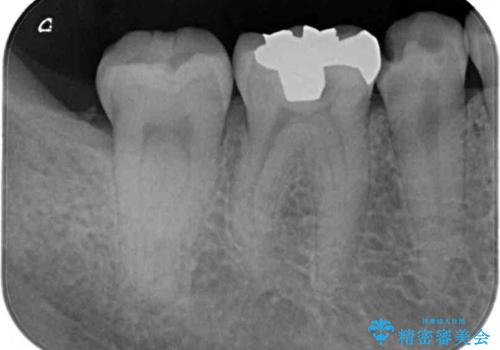

他院で治療中の歯 ゴールドインレーによる修復治療

- 近医にて虫歯治療中に転院を希望とのことで来院された患者様です。

左上奥と右下奥に治療中の歯があり、虫歯を取っている途中で仮詰めの材料が充填されている状態でした。

当初はセラミックインレーによる修復治療を希望されいましたが、カウンセリングの結果、審美性よりも安定性を優先され、PGAインレー(ゴールドインレー・白金加金合金インレー)による治療を行うこととしました。

仮詰め材を外すと虫歯が残っていたので、全てを取り除いた後に、ゴールドインレーの型どりを行いました。